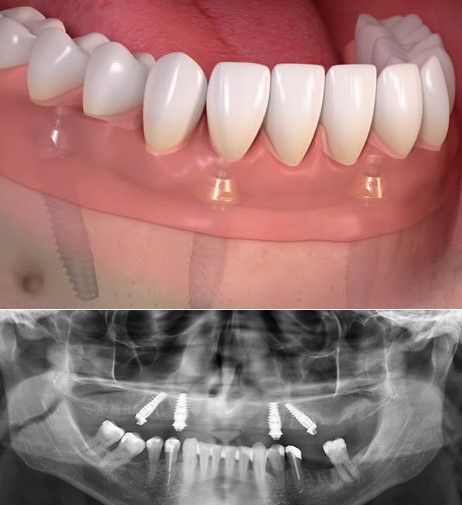

All on 4 is the optimal solution for those who have lost or are about to lose all of their upper and/or lower teeth. With this procedure, doctor will place 4 implant cyliner into your jawbone and then the new bridge or denture will be placed, you can come as close to having a new set of permanent teeth as is currently possible.

(4 implant will be placed into jawbone with permanent denture above)

Noted: Beside all on 4, customer can also choose all on 5 or all on 6, these two methods are the same to all on 4 but with 5 or 6 implant cylinder will be placed

(All on 6 are the same as all on 4, the only different is 6 implant will be placed instead of 4)